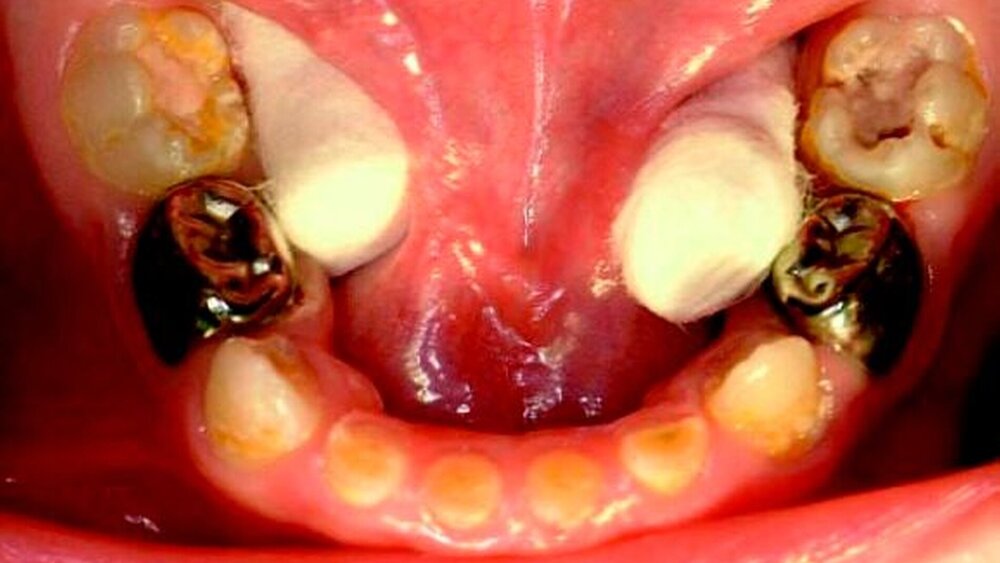

Bei der Inspektion der Mundhöhle des Kindes zeigte sich ein altersentsprechender Durchbruchstand der Zähne (Abbildung 1). Sämtliche Zahnflächen wiesen Beläge auf. Alle zwölf Zähne zeigten Zahnhartsubstanzdefekte. Die Schneidezähne des Oberkiefers waren am stärksten betroffen. Diejenigen Zahnschmelzanteile, die erst seit kurzer Zeit innerhalb der Mundhöhle standen, zeigten keine Veränderungen. Im Bereich des Zahnes 51 bestand im Vestibulum eine fluktuierende Schwellung. Auf Druck entleerte sich Pus aus dem gingivalen Sulkus (Abbildung 1b). Aufgrund des großen Behandlungsbedarfs und des geringen Alters wurde eine zahnärztliche Behandlung in Intubationsnarkose angeboten und zeitnah durchgeführt. Dabei wurde der entzündete Schneidezahn 51 entfernt, sämtliche anderen Schneidezähne mit Füllungen und die ersten Molaren mit konfektionierten Kronen versorgt. An den verbliebenen Oberkiefer-Schneidezähnen wurde jeweils eine Wurzelkanalbehandlung durchgeführt. Bei einer postoperativen Kontrolle nach einer Woche war der Patient beschwerdefrei. Weitere Vorstellungen erfolgten nicht.

Weitere drei Monate später wurde der nun 31 Monate alte Junge mit Schmerzen wieder vorgestellt. Nach der ersten Narkosebehandlung wurde abgestillt. Außerhalb der Mahlzeiten erhielt das Kind verdünnte Fruchtsäfte. Diese wurden auch zum Einschlafen und während der Nacht gegeben. Zum Zähneputzen wurde ausschließlich fluoridfreie Zahncreme verwendet. Der intraorale Befund ergab kariöse Läsionen an allen zweiten Molaren, Eckzähnen und Unterkiefer-Schneidezähnen. Die mit konfektionierten Kronen versorgten Zähne waren unauffällig. Erneut wurde eine Sanierung in Intubationsnarkose vorgeschlagen. Diese wurde zwei Monate später durchgeführt (Abbildung 2). Intraoperativ zeigte der Zahn 81 eine deutliche Lockerung sowie radiologisch eine periapikale Aufhellung und wurde daher entfernt. Die Zähne 55, 75 und 85 wurden mit konfektionierten Kronen, sämtliche anderen Zähne mit adhäsiven Füllungen versorgt. Der Zahn 71 wurde endodontisch behandelt. Der behandelnde Kinderarzt bestätigte, dass alle kinderärztlichen Vorsorgeuntersuchungen von der Mutter wahrgenommen wurden und keine auffälligen Befunde vorlagen.

Durch tief zerstörte, kariöse Zähne leidet das Kind unter chronischen Schmerzen. Dies kann zur Beeinträchtigung des Schlafens, des Lernens und der Teilnahme an täglichen Aktivitäten führen. Es hat Schwierigkeiten beim Essen, weswegen insbesondere kauaktive Nahrungsmittel gemieden werden. Die weitere Zahnpflege ist erschwert, da die Zähne berührungs- und kälteempfindlich sind. Kariöse Zähne der ersten Dentition steigern das weitere Kariesrisiko, da die Keimzahl im Speichel und auf den Zahnoberflächen deutlich erhöht ist. Kinder mit kariös zerstörten Gebissen zeigen ein verzögertes Wachstum. Kariöse Destruktionen der Frontzähne führen zur Beeinträchtigung der Sprachentwicklung und zu Hänseleien durch andere Kinder [1, 2, 15, 16, 22, 32]. Chronisch entzündete Zähne führen zu einer Keimverschleppung in den periapikalen Raum. Im Weiteren können sich Fisteln, Abszesse (Abbildung 1a) und Mineralisationsstörungen an den nachfolgenden Zähnen bilden. Müssen Zähne der ersten Dentition vorzeitig entfernt werden, kann es zu Durchbruchstörungen der nachfolgenden Zähne bis hin zu deren Retention kommen. Es können sich Anomalien der Zahnstellung, der Okklusion und der Kieferposition entwickeln. Dieses kann zu Dysgnathien und zur Annahme von Dyskinesien führen. Beides hat langwierige kieferorthopädische Behandlungen zur Folge [29, 30].